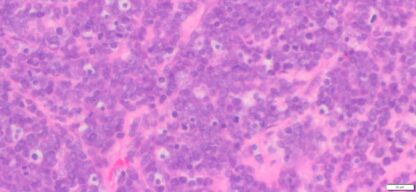

| HumanOvary | Human Ovary B-Lymphoblastic leukemia (ALL) | Male/19 | 90% | N/A | N/A | Diffusely (+): PAX-5,CD10, TdT

Weak (+) : CD79,CD34 and CD45 Neg: CD20,CD3 and MPO |